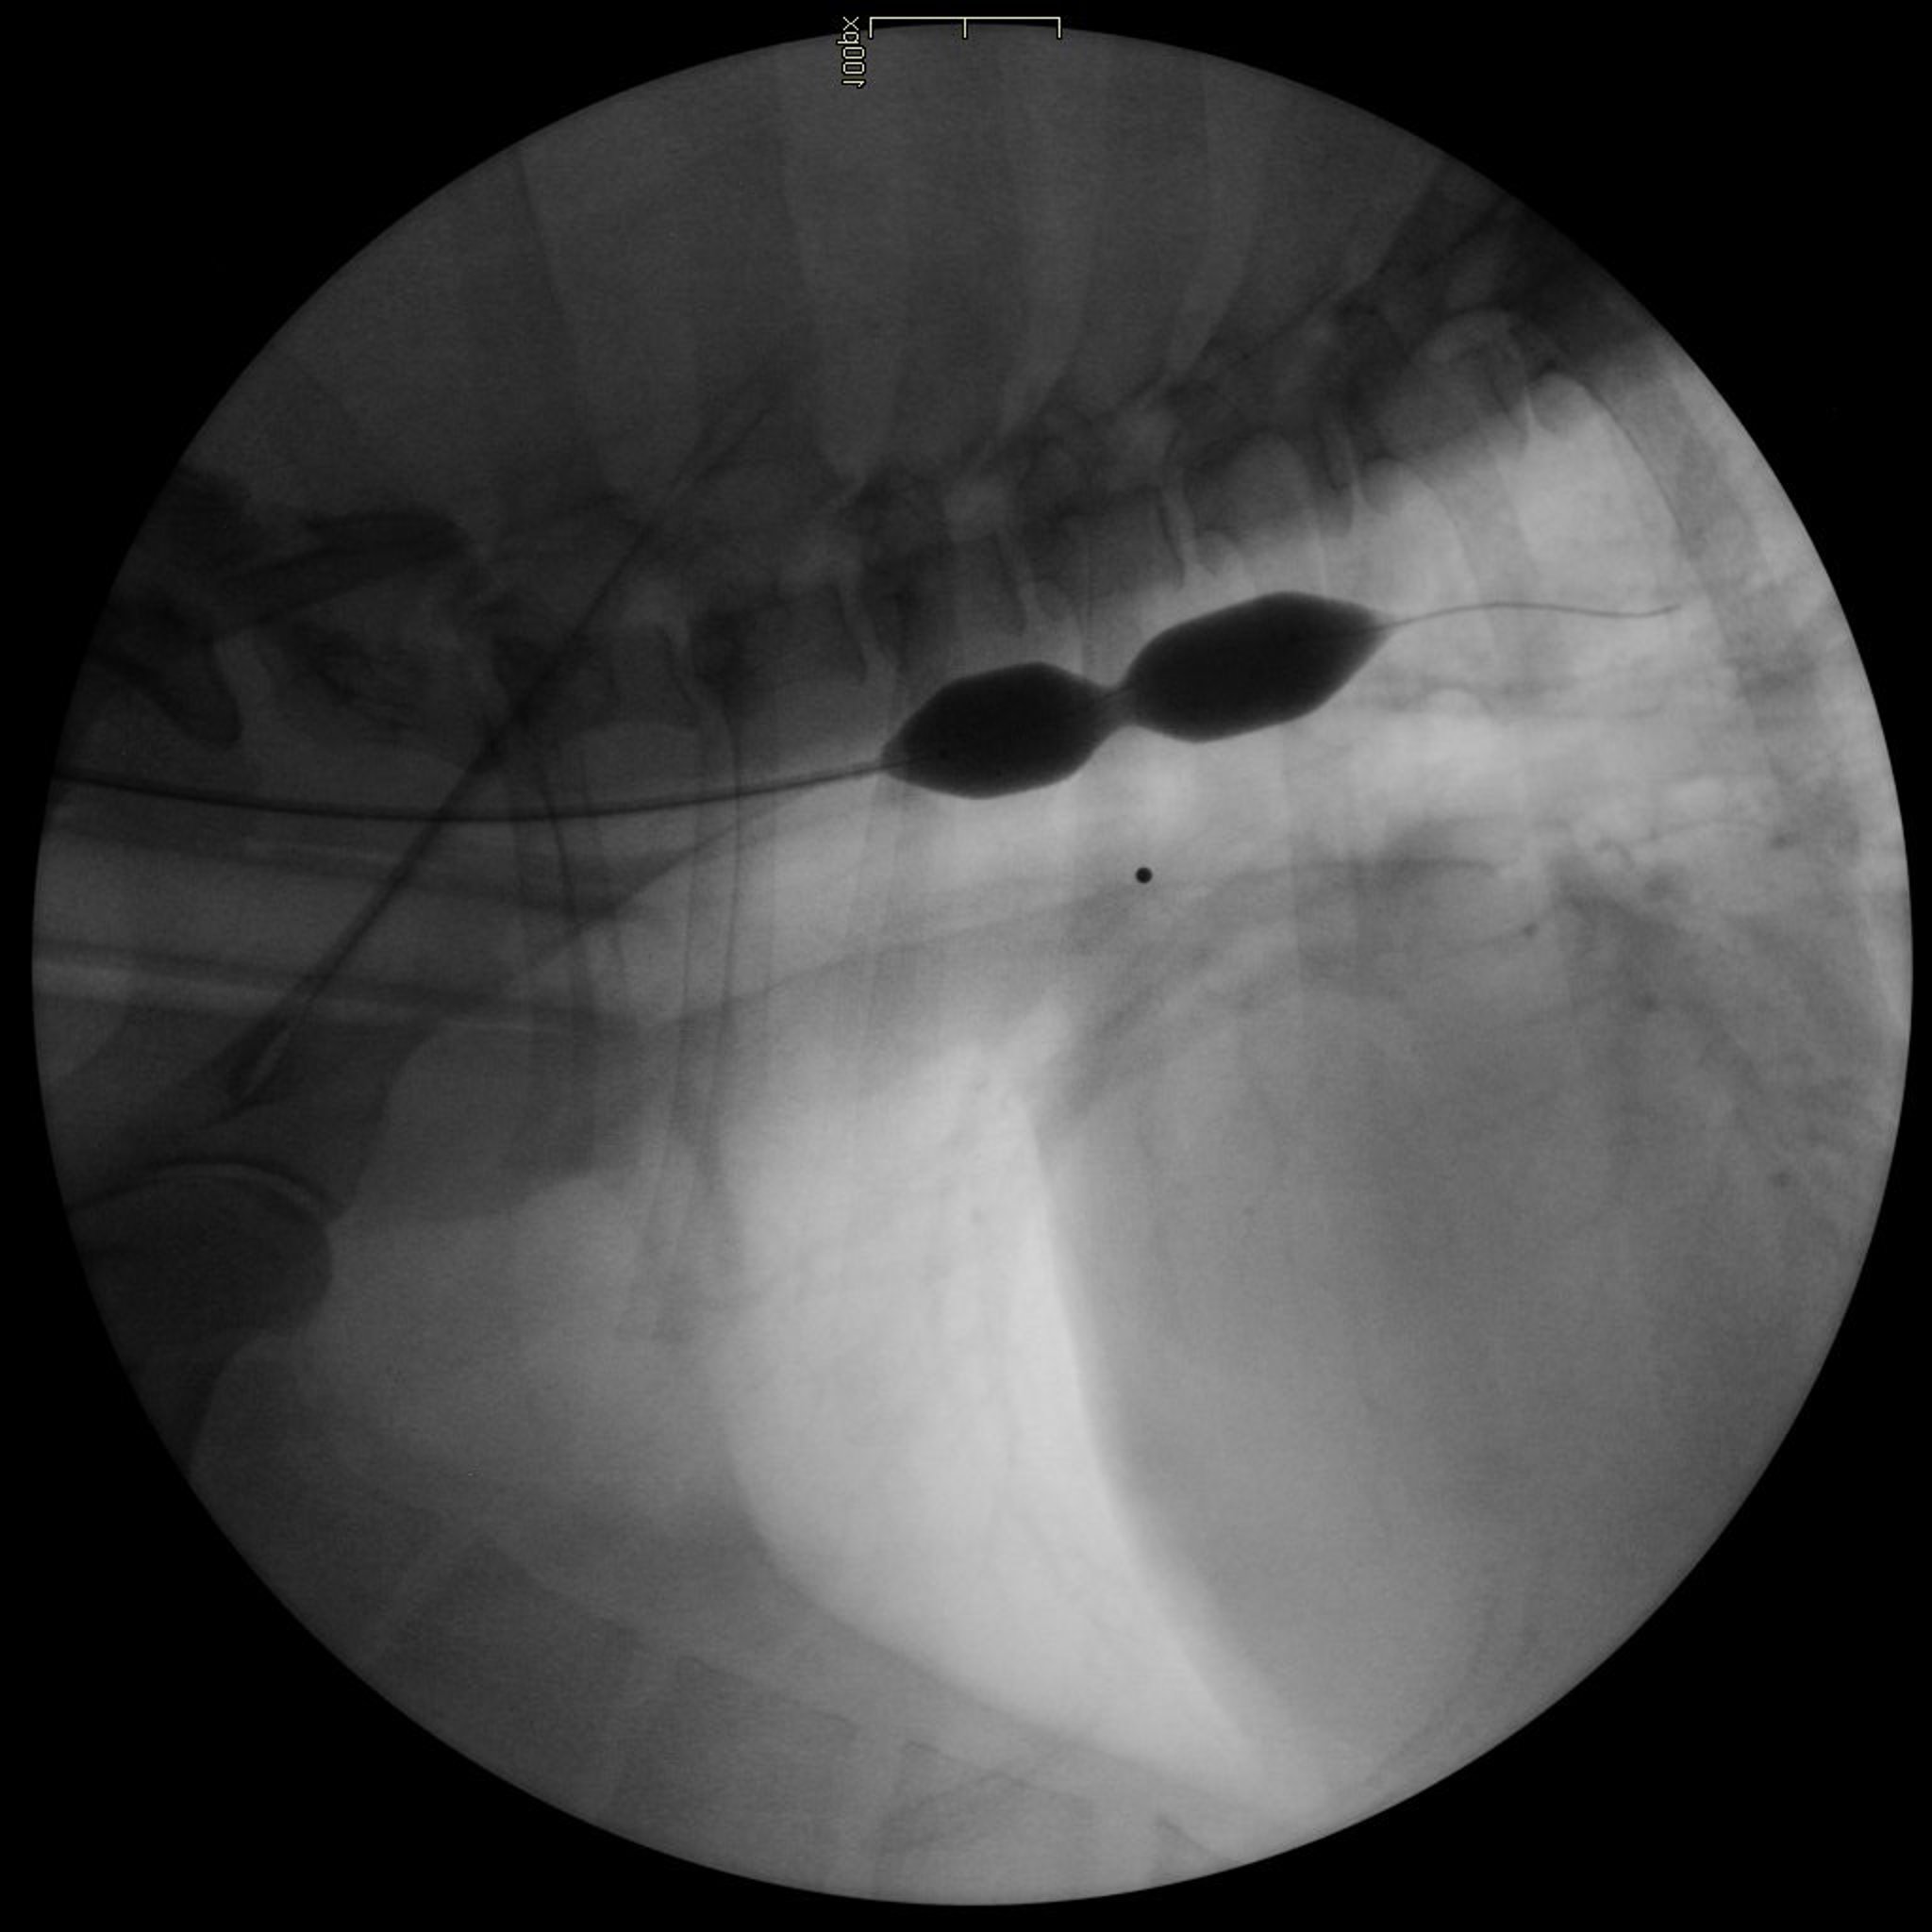

Vista fluoroscópica (lateral) del tórax de un perro, que muestra una estenosis esofágica dilatada.

Cortesía de Alex Zur Linden.